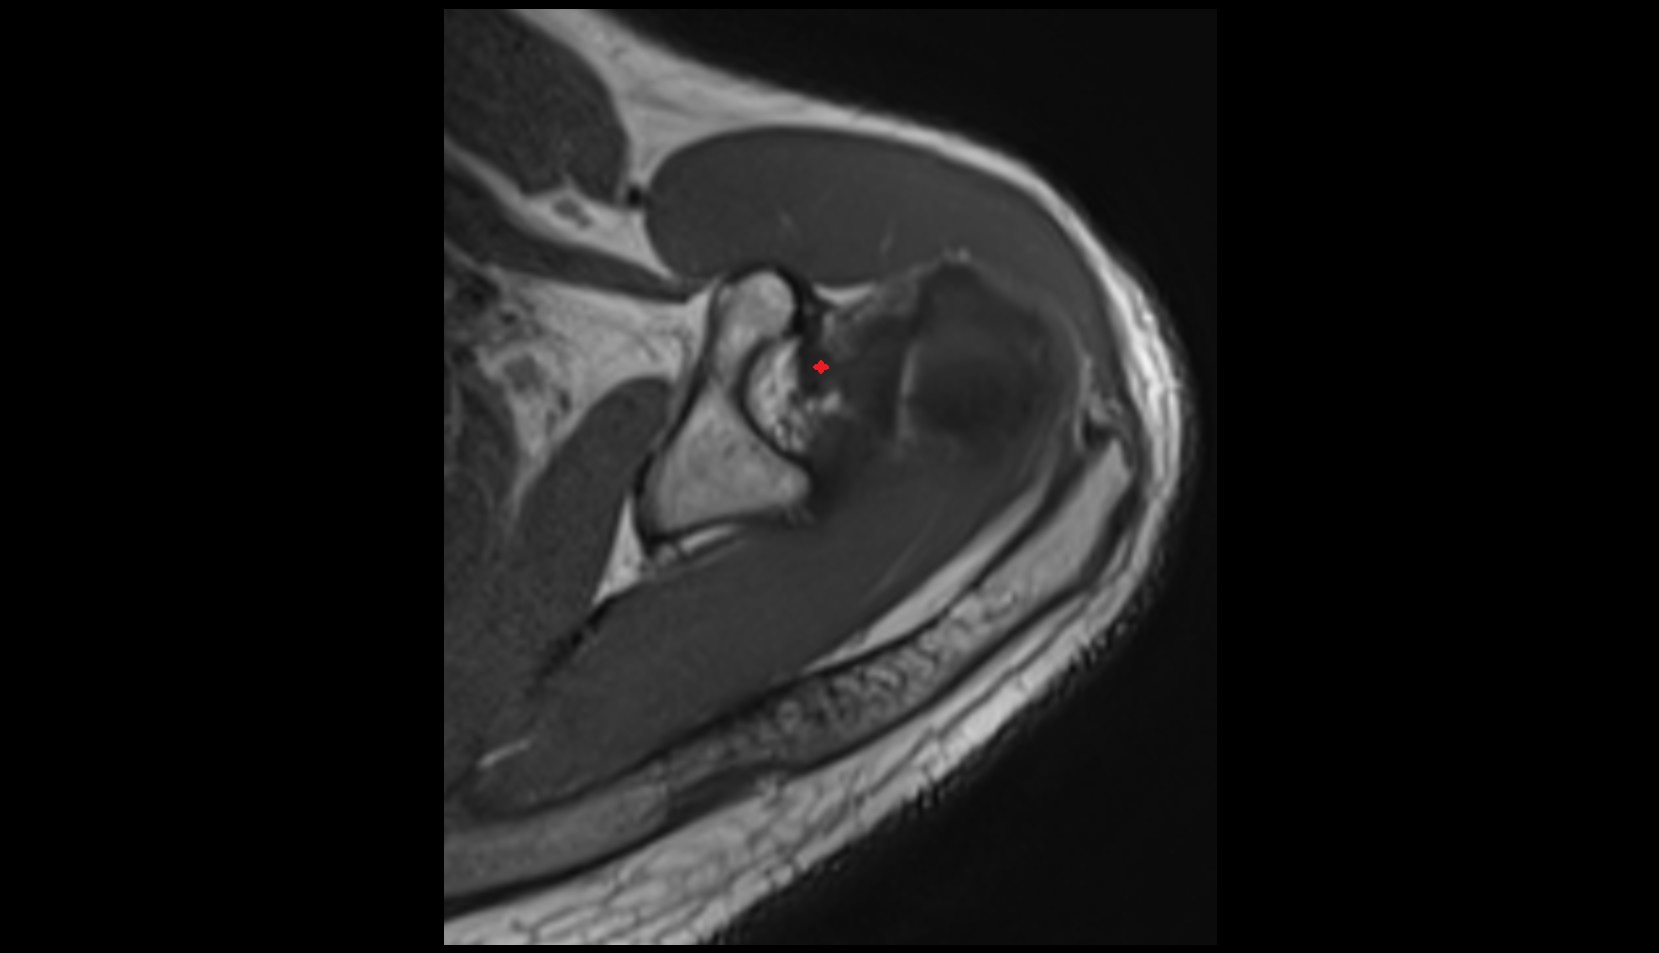

- Temporomandibular joint

- Articular disc of temporomandibular joint

- Mandibular condyle

- Mandibular fossa

- Superior head of lateral pterygoid muscle

- Inferior head of lateral pterygoid muscle